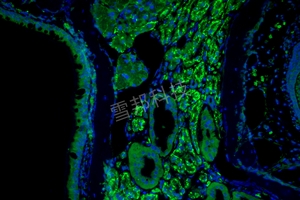

荧光拍照

产品描述